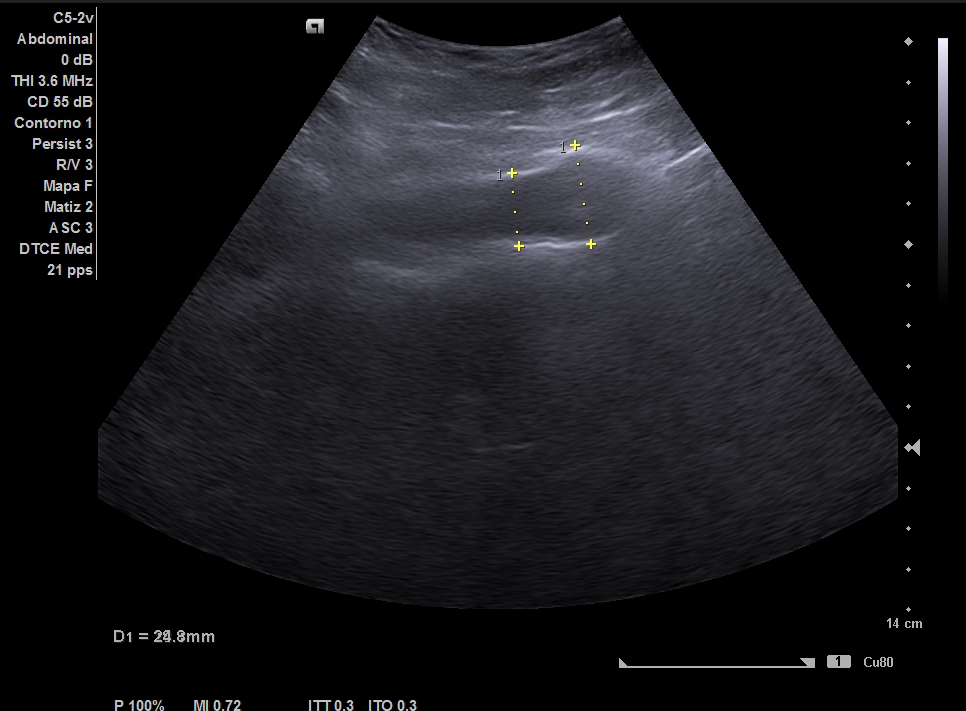

Parenquima hepatico sin alteraciones, vesícula biliar sin imagenes hiperecoénicas en interior. Pancreas visible en parte, sin alteraciones. Asimetría entre ambos riñones compatible variante de la normalidad RI. Llama la atención dilatación ilíaca derecha al comparar con contralateral y con aorta abdominal distal. Compatible con dilatación aneurismática ilíaca derecha.

El diagnóstico diferencial del Aneurisma Ilíaca con: Displasia fibromuscular u otra patología del tejido conectivo, lúes o tuberculosis entre otros. Toda dilatación que sobrepase el 50% del diámetro del vaso se considera aneurismática. Por la edad no se plantea el origen ateromatoso.